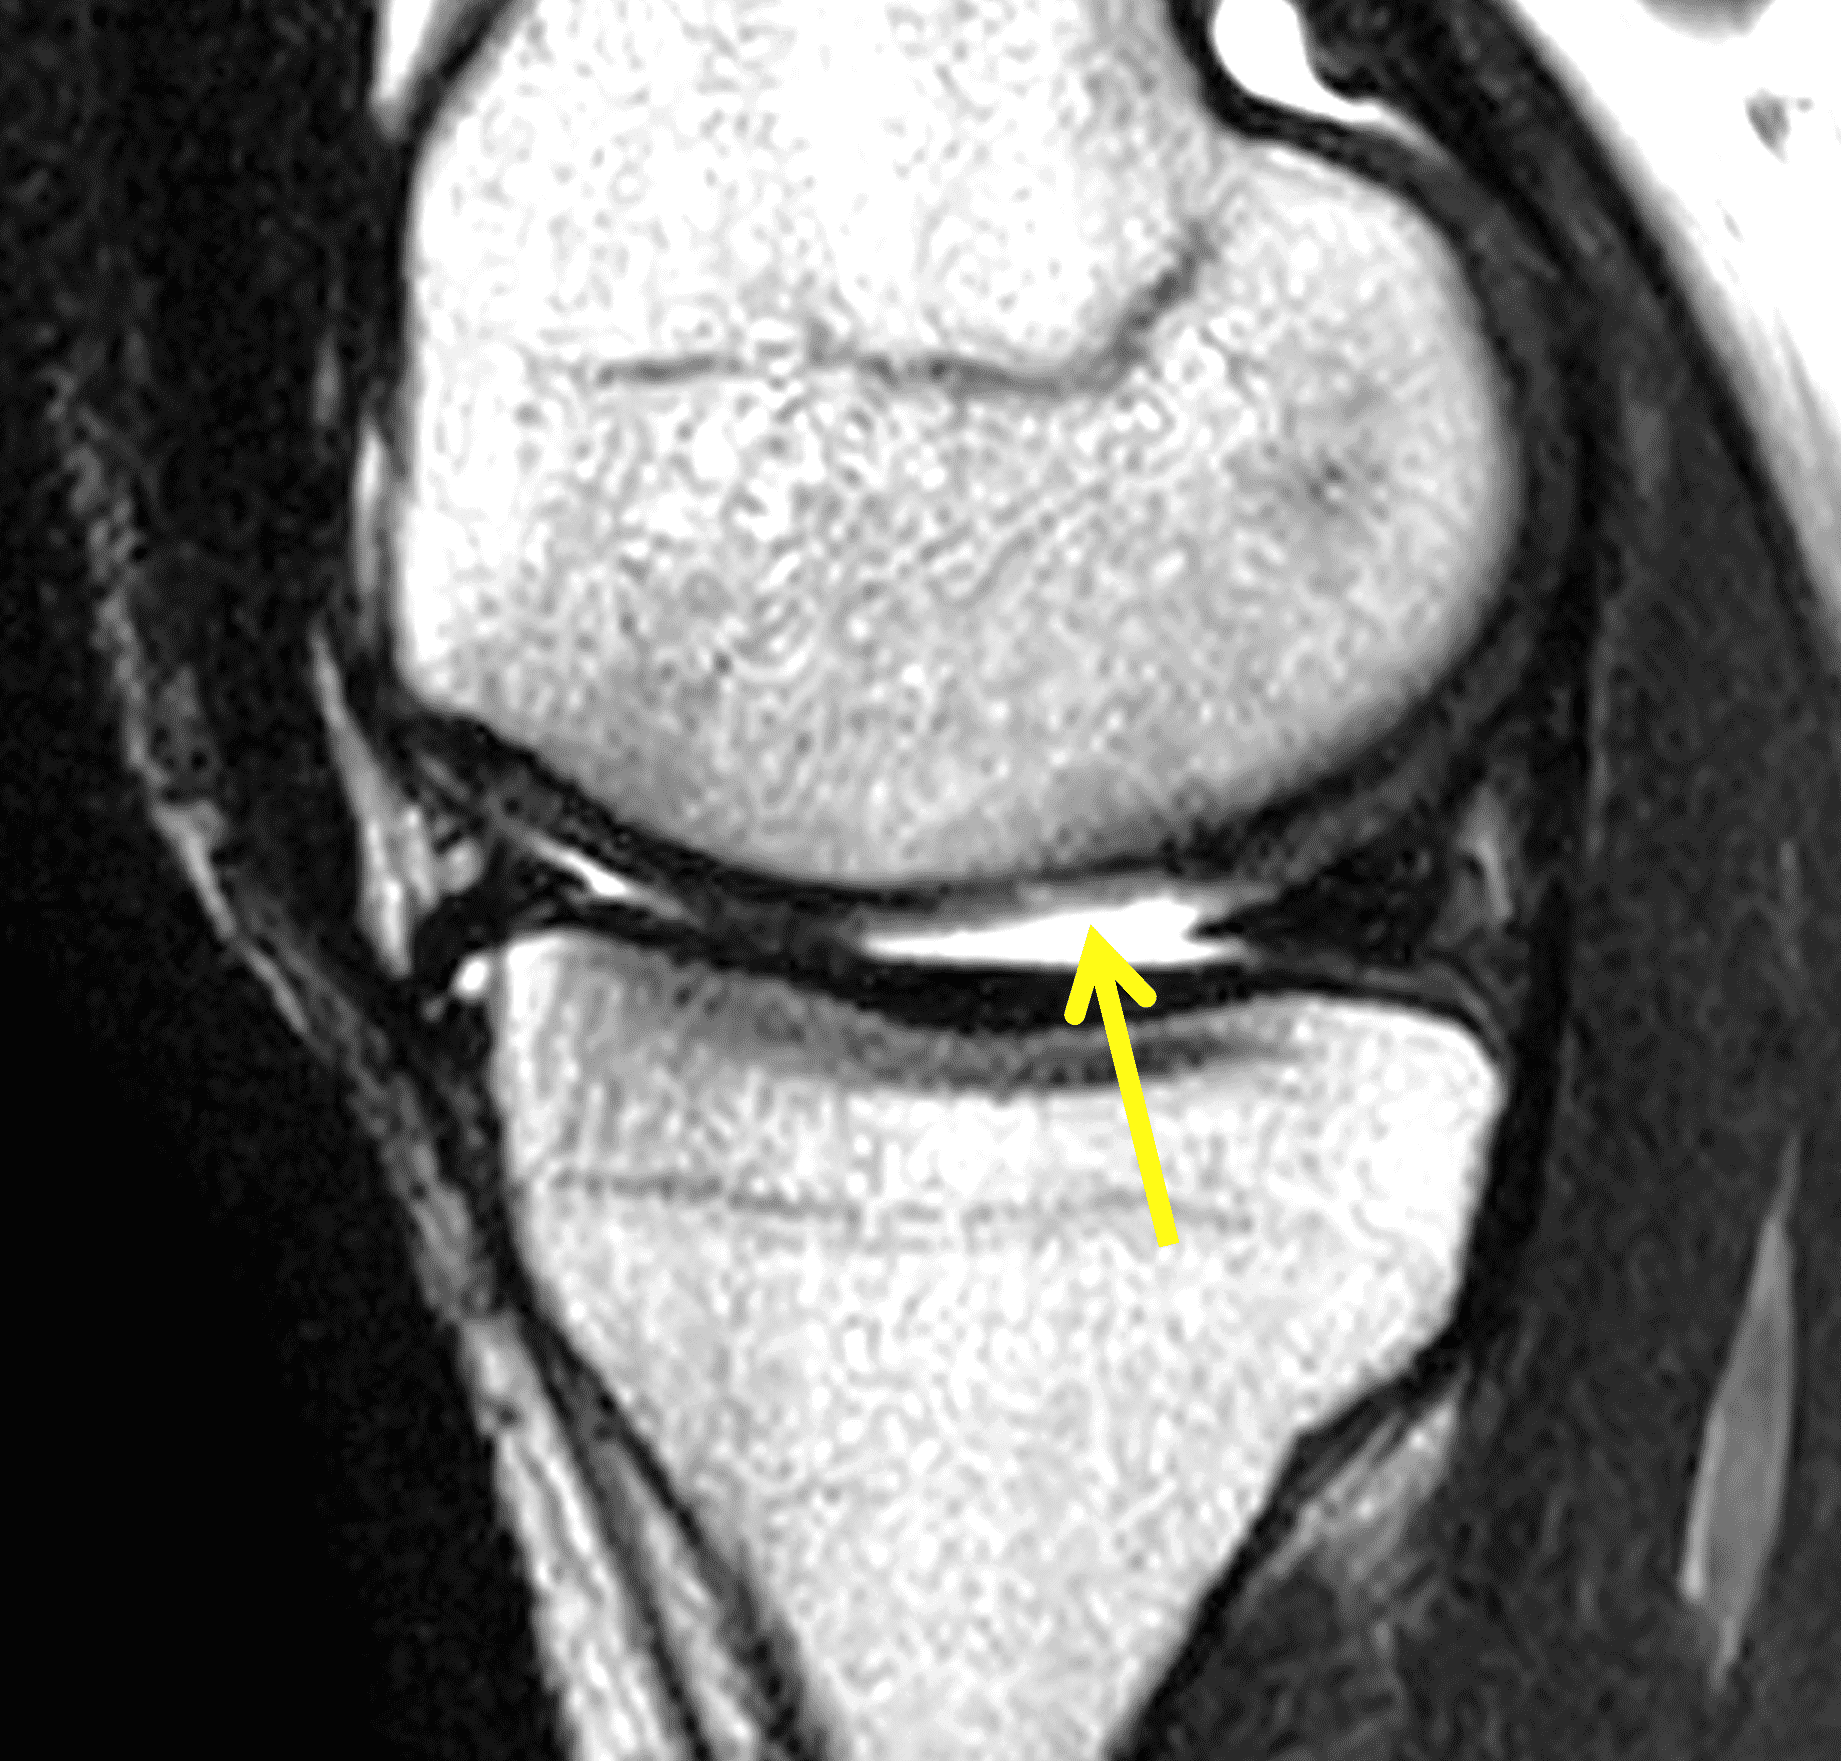

A 32-year-old man suffered a traumatic chondral injury to the medial femoral condyle that was treated with an osteochondral allograft 20 months previously. Representative images from a current knee MRI include (1A) coronal fat-suppressed fluid-sensitive and sagittal (1B) T1-weighted, (1C) proton density-weighted, and (1D) T2-weighted sequences. Are the post-operative MRI findings normal and expected, or abnormal and pathologic? Based on these images, would you characterize the procedure as a success or failure?

Figure 2: (2A) On the coronal image, the margins of the osteochondral graft are faintly visible (arrowheads). Both the graft and underlying bone show mild marrow edema, an expected finding. (2B) The T1-weighted image shows continuity of the marrow in the graft (asterisks) with the underlying bone, indicating osseous integration. A bioabsorbable pin (arrow) used for graft fixation is partly visible. (2C) The proton density-weighted image shows a low signal intensity seam (black arrow) between the native cartilage and transplant, as well as a defect in the subchondral bone plate of the graft (red arrow) where the pin was drilled, both normal findings. (2D) The T2-weighted image shows a smooth, congruent articular surface (arrows), restoring the normal anatomy, and a tiny subchondral cyst. No findings are present to suggest graft failure. The patient’s current symptoms were attributed to pathology elsewhere in the joint (not shown).

Successful osteochondral allograft procedure.

The postoperative imaging appearance of osteochondral allografts is similar to autografts (Figure 2).33 The subchondral bone plate of the donor and recipient sites do not have to match, but the articular surface should be congruent. Grafts that fail to incorporate by one year have a poor prognosis. Persistent marrow edema (beyond 12 months), a thick graft interface containing cysts or fluid, and subsidence of the graft are associated with poor osseous healing and worse outcomes. Extensive host marrow edema and severe synovitis may be a clue to immunologic rejection of the graft (Figure 18).21, 34